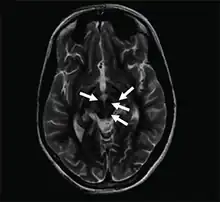

| Face of the giant panda sign | |

| Axial T2-weighted MRI of the brain at the level of the midbrain showing the characteristic ‘face of the giant panda’ sign, with normal red nuclei and substantia nigra (pars reticulata) against a background of hyperintensity in the tegmentum, as well as hypointensity of the superior colliculi | |

The face of the giant panda sign, panda sign of the midbrain or double-panda sign is a characteristic "panda's face" appearance in magnetic resonance imaging (MRI) images of people with Wilson's disease. Along with Kayser–Fleischer rings, the sign is helpful in diagnosis.[1]

While the sign is most common in Wilson's disease, it has been rarely reported in acute disseminated encephalomyelitis,[2] rabies encephalopathy,[3] toxic leukoencephalopathy[4] and Leigh syndrome.[5]